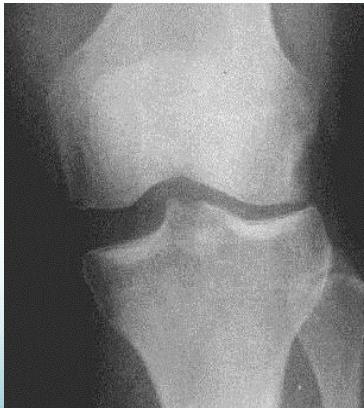

Diagnostic Studies for MCL

X-ray

- May show avulsion fracture

- Stress Film: Shows ligament laxity